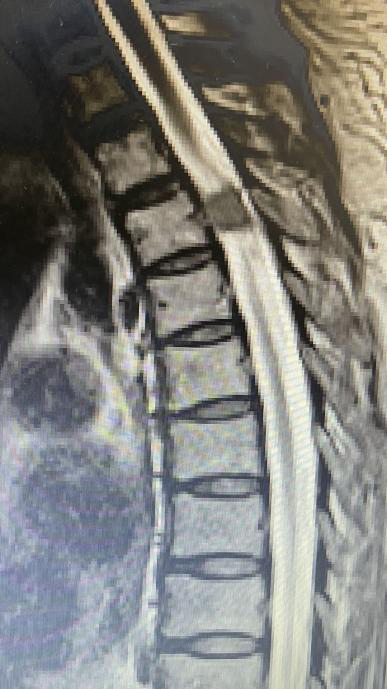

接诊的骨科主任医师徐杰让王奶奶做了检查,发现导致王奶奶双腿麻木的元凶,竟然是因为她的胸椎管内悄悄地长了一个脊膜瘤。

这个肿瘤必须手术切除,可小小的椎管内长了肿瘤,要在手术中准确找到它的位置,显然不是件容易的事。倘若稍有不慎,还可能损伤脊髓,延长术后恢复时间。

敲定了手术方式,手术如期进行。在徐杰的引导下,“天玑”灵活地挥动着机械臂,紧贴肿瘤边缘,磨出一个近似长方体的区域,很快就将肿瘤位置锁定。随后,徐杰娴熟地运用他自创的手术方式切除了整个肿瘤,术后影像显示肿瘤切除范围与术前规划几乎完全一致。

手术时,医生将病人的三维CT图像导入机器人图像系统,主刀医生在机器人系统的计算机上,用鼠标规划好在脊椎椎板上开窗的最小边界和最佳斜率方向,路径边界避开了重要的结构并保留脊柱关节突;随后,启动机器人的机械臂,自动精确走位到该边界,利用携带的磨钻直接在脊椎上开一小窗。然后,医生在显微镜下用显微外科技术打开脊髓神经的硬膜,完整切除肿瘤,该肿瘤为钙化性脊膜瘤。